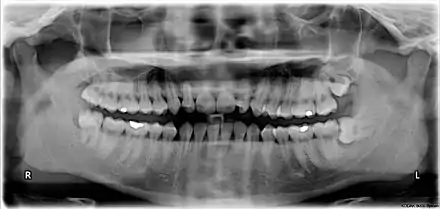

ضرسا العقل في الجزْئينِ العلوي اليساريّ (في الصورة من اليمين) والعلوي اليمينيّ (في الصورة من اليسار) متراصّان نحو الزاوية الخلفية. أما ضرس العقل السفليّ اليساري فمتراصّ بشكل أفقي، وأمّا اليميني فمتراصٌّ بشكل عموديّ.